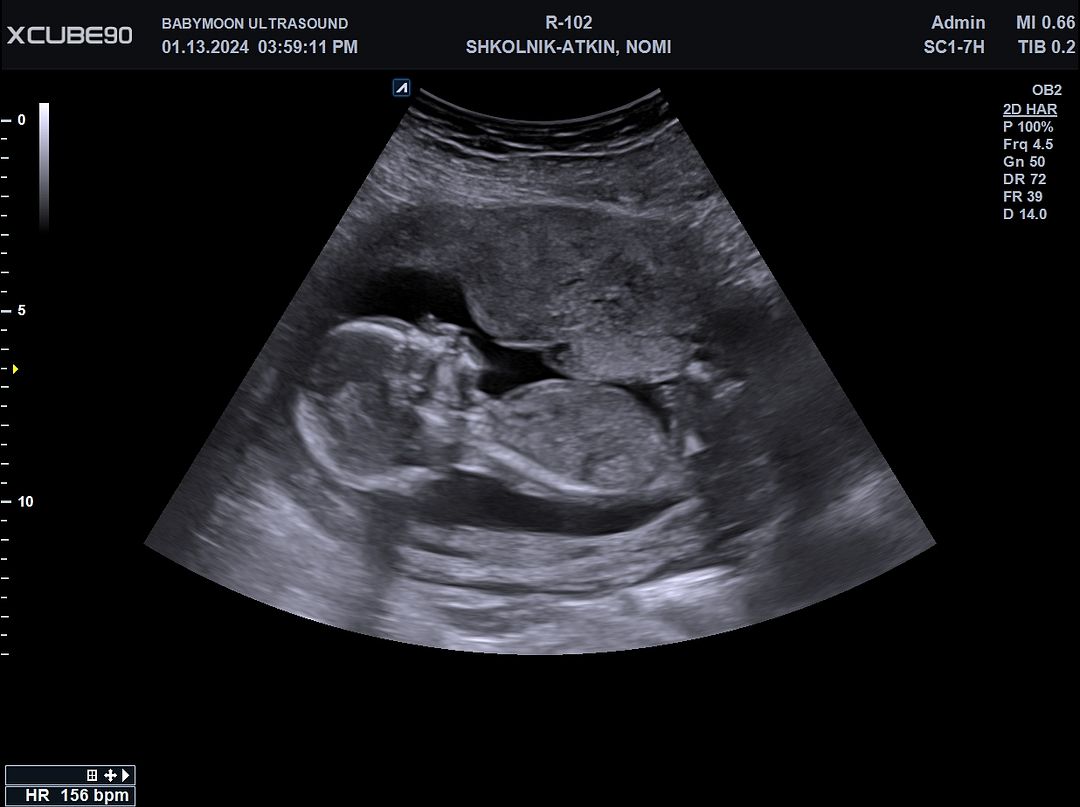

What position is this fetus in?

Cephalic